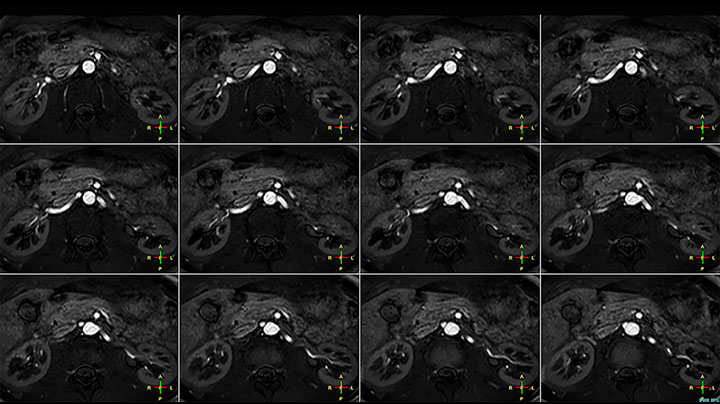

Non-contrast MRA of renal arteries

Imaging the renal arteries without contrast agent on Prodiva 1.5T.

TRANCE MIP

eMIP native Angio RL